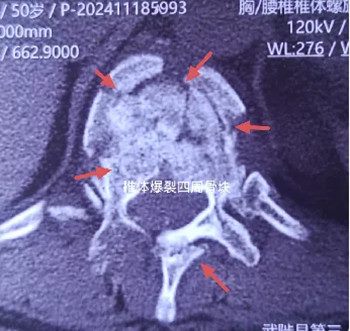

50岁的王女士最近不慎由高处坠落,背部着地,腰背部剧烈疼痛,双腿不能活动,送往当地卫生院就诊,CT检查显示胸11椎体爆裂骨折,骨块压迫脊髓。患者病情危重,严重胸椎骨折脊髓损伤可能导致终身瘫痪,家属万分着急,限于镇卫生院医疗条件不足,当地兄弟单位紧急联系郑州大学第五附属医院骨科二病区(脊柱脊髓损伤治疗中心),希望患者能得到更好的治疗。